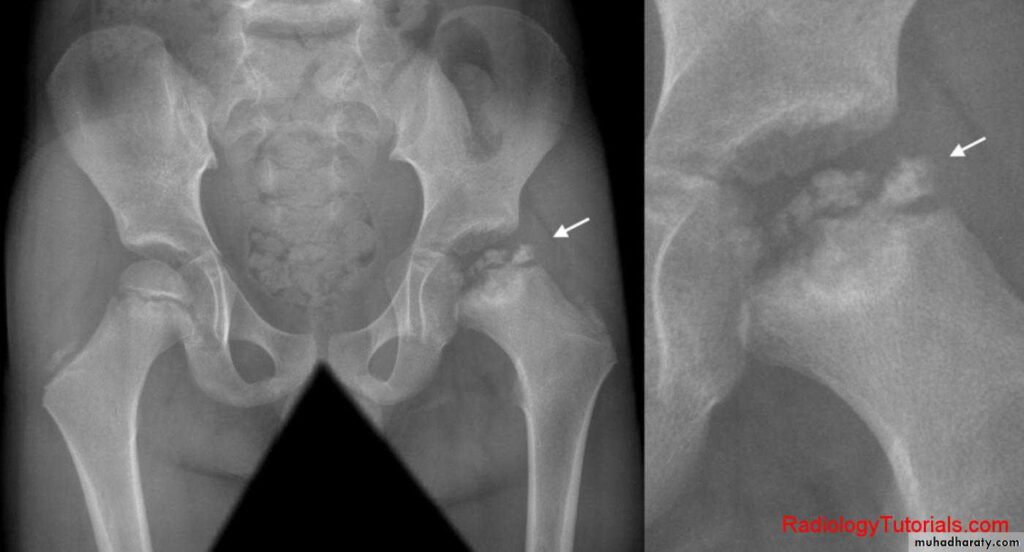

Exames de imagem

Se houver suspeita de alterações mais complexas, o ortopedista pode solicitar exames, como:

- Ultrassonografia de quadril: muito útil para identificar sinovite transitória ou excesso de líquido na articulação.

- Radiografia: indicada para avaliar a estrutura óssea e diagnosticar doenças como a Doença de Perthes.

- Ressonância magnética: utilizada em casos específicos para observar detalhes das articulações, músculos e cartilagens.

- Radiografia (Raio-X):

Importante para avaliar a estrutura óssea. Ajuda a identificar doenças como a Doença de Perthes e outras alterações ortopédicas.